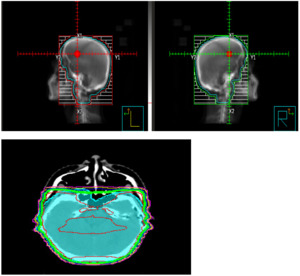

For CRB, CT simulation was performed using head mask; radiation fields consisted of two lateral opposing 6 MeV beams, including the whole skull content of brain and meninges. The anterior part was extended to include the meningeal cover of optic nerves up to the optic discs and down to the C2-C3 vertebral level. Shield was added to protect lens and oral cavity. This was a 95% coverage of the planning target volume (PTV) with homogenous isodose lines (figure-1). CRB was completed within two weeks prior to initiation of TBI. The CRB dose consisted of 12.6 cGy over 7 fractions by 3D conformal radiotherapy regardless of age, not to exceed 30cGy with prior cranial radiation. Three patients received a reduced dose of CRB of 8cGy. Graft-versus-host disease (GvHD) prophylaxis included either cyclosporine or tacrolimus and mycophenolate mofetil or methotrexate. ATG 2.5mg/kg was given in mismatched related donor transplants (MMRD) and PTCy 50mg/kg on day+3 and day+4 in haploidentical alloHCT.

_(crb__cranial_radiation_b.png)